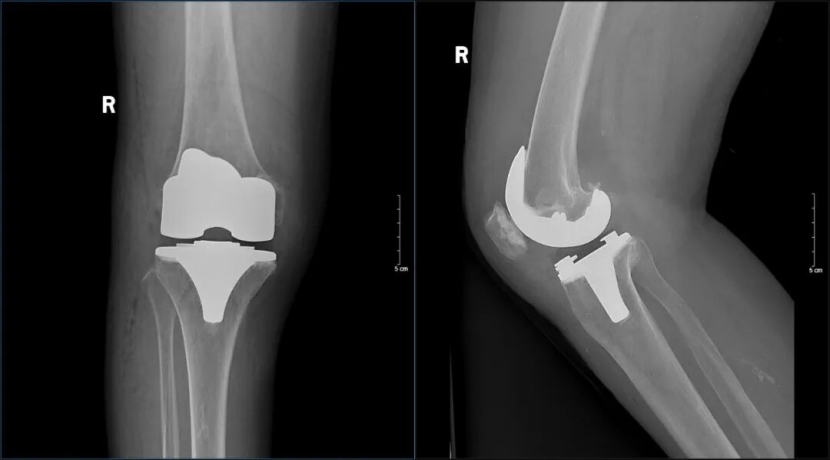

在手术室及麻醉科团队的密切配合下,杨学良主任凭借丰富经验和精准操作,成功为患者实施右侧人工全膝关节置换术。术中精细松解、假体安装稳固,畸形得到即刻矫正。术后患者恢复良好,关节活动度显著改善。